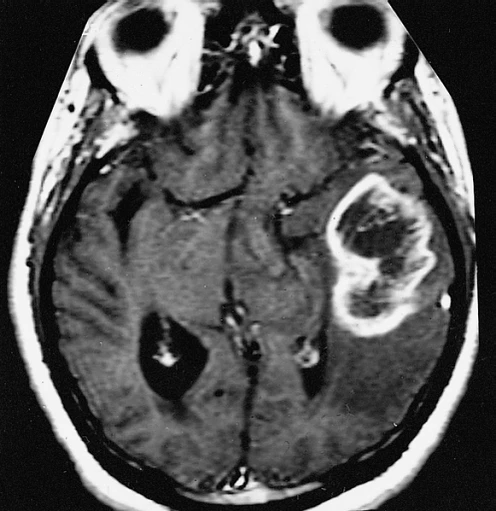

При магнитно-резонансной томографии выявляются множественные или солитарные опухолевидные очаги. Супратенториальные поражения локализуются в перивентрикулярном белом веществе, фронтальной и теменной долях и височной доле. Наблюдаются очаги с полным или периферическим (кольцевидным) усилением после введения контраста. Присутствуют признаки перифокального отёка с минимальным масс-эффектом, неоднородная структура очагов, а также признаки ограничения диффузии. В спинном мозге редко выявляются неконтрастируемые очаги на уровне 2—3-го шейного, 1—2-го и 9-го грудного позвонков. Отсутствие патологических изменений в шейном и грудном отделах спинного мозга при наличии множественных очагов в головном мозге является более характерной диагностической особенностью данного заболевания[6].

- При магнитно-резонансной томографии (≥1,5 Тесла) выявляется один или несколько церебральных очагов, причём хотя бы один из них проявляет масс-эффект, с отёком или без него, и имеет размер ≥2 см в одном из измерений.